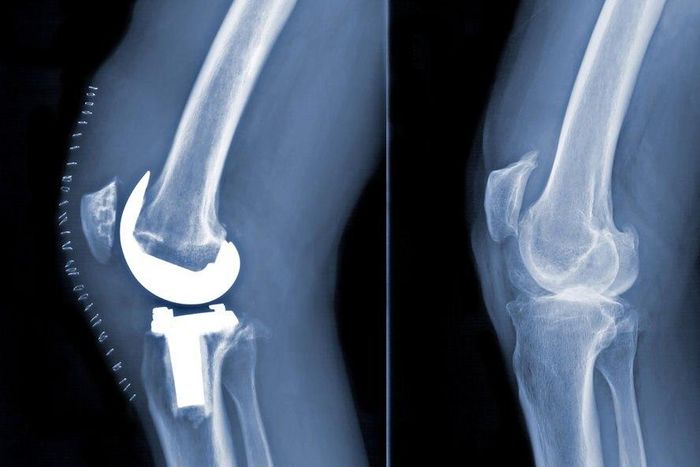

Medicare has several bundled payment programs for hip and knee replacements — the most common type of Medicare procedures — and associated care that takes place within 90 days. This includes the operation itself, as well as follow-up rehabilitation (also known as post-acute care). In theory, if doctors and hospitals get one payment encompassing all this, they will better coordinate their efforts to limit waste and keep costs down.

One possible issue would be if, despite saving money per procedure, health care providers wastefully increased the number of procedures — replacing hips and knees that they might not otherwise. A related concern is if hospitals try to increase profits by nudging services toward patients who may not need a procedure as much as patients with more severe and more expensive conditions. An average joint replacement costs $26,000, split almost equally between the initial procedure and post-acute care. But more expensive cases can be $75,000 to $125,000 — a costly proposition for hospitals.

A recent study published in JAMA examined whether the volume of Medicare-financed hip and knee replacements changed in the markets served by hospitals that volunteered for a bundled payments program, relative to markets with no hospitals joining the program. It found no evidence that the bundled payment program increased hip and knee replacement volume, and it found almost no evidence that hospitals skewed their services toward patients whose procedures cost less.

Another new study in JAMA examines a mandatory, randomized trial of bundled payments. On April 1, 2016, Medicare randomly assigned 75 markets to be subject to bundled payments for knee and hip replacements and 121 markets to business as usual. This policy experiment, known as the Comprehensive Care for Joint Replacement program, will continue for five years. The JAMA study analyzed just the first year of data.

The study found that bundled payments reduced the use of post-acute care by about 3 percent, which is less than what prior studies found. “Those prior studies weren’t randomized trials, so some of the savings they estimate may really be due to which hospitals chose to participate in bundled payment programs,” Finkelstein said. Despite reduced post-acute care use, the study did not find savings to Medicare once the costs of paying out bonuses were factored in. The study also found no evidence of harm to health care quality, no increase in the volume of hip and knee replacements, and no change in the types of patients treated.